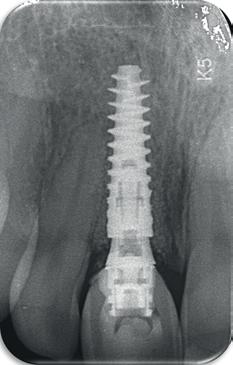

11. Röntgenfoto ter controle van de plaatsing en de angulaire. Dit bone-level implantaat werd 4 mm onder de weke delen geplaatst.

13. Röntgenfoto ter controle van de pasvorm van de direct geplaatste tijdelijke kroon.

14-16. Patiënt presenteerde zich met een forse zwelling en botverlies rondom het implantaat.

17. Verwijderen van de tijdelijke kroon.

18. Explantatie van het implantaat.

19. Curettage van de alveole in combinatie met curettage totdat er geen exsudaat meer was.

Het kantelpunt: de patiënt komt terug (afbeelding 14-16)

De patiënt meldde zich opnieuw in de praktijk met klachten: pijn, zwelling en een duidelijke intraorale infectie. Bij inspectie zag ik direct een probleemhet ging om een klassiek beeld van peri-implantair botverlies met een abces. Dit patroon van botverlies en infectie spiegelde sterk de gevolgen van thermische trauma.

Op de röntgenfoto’s zag ik wat ik al vreesde: er was botresorptie rond het implantaat. De zachte weefsels waren ontstoken en het implantaat vertoonde teke-

nen van mobiliteit. Op dat moment wist ik precies wat er was misgegaan.

Dit was geen kwestie van een verkeerde occlusie of een slecht gekozen abutment. Dit was een puur biologisch probleem, veroorzaakt door mijn onderpreparatie van de osteotomie en de daarmee gepaard gaande botnecrose of compressie. Mijn streven naar immediaat belasten had me verblind, en ik had een fundamentele regel van de implantologie genegeerd: bot moet kunnen ademen. Op dat moment had ik geen andere keuze dan de situatie te herstellen.

Herstel: terug naar de basis (afbeelding 17-19)

De behandeling van dit mislukte implantaat volgde een stapsgewijze aanpak:

1. Explantatie van het implantaat. Het implantaat werd voorzichtig verwijderd, waarbij ik probeerde zoveel mogelijk bot te behouden.

2. Curettage en reiniging. De alveole werd intensief gecuretteerd en gespoeld tot er geen exsudaat meer aanwezig was. Met goede communicatie kon ik de patiënt overtuigen om 3 maanden later terug te komen voor de botopbouw, zodat we het beste fundament konden creëren voor een duurzame oplossing.

3. Botopbouw met GBR. Ik koos voor een combinatie van allograft, xenograft en autograft om de botdeficiëntie aan te pakken. Dit mixen van bottypes creëerde een optimale omgeving voor regeneratie.

4. Twee-fasen implantologie. Dit keer nam ik geen risico’s. In plaats van een immediaat implantaat koos ik voor een delayed plaatsing. Het bot kreeg eerst de tijd om te rijpen voordat ik een nieuw implantaat plaatste. Deze keer verliep de procedure zonder problemen. Het bot herstelde zich zoals verwacht en na enkele maanden kon ik een nieuw implantaat plaatsen, met een correcte osteotomie en zonder onnodige compressie.